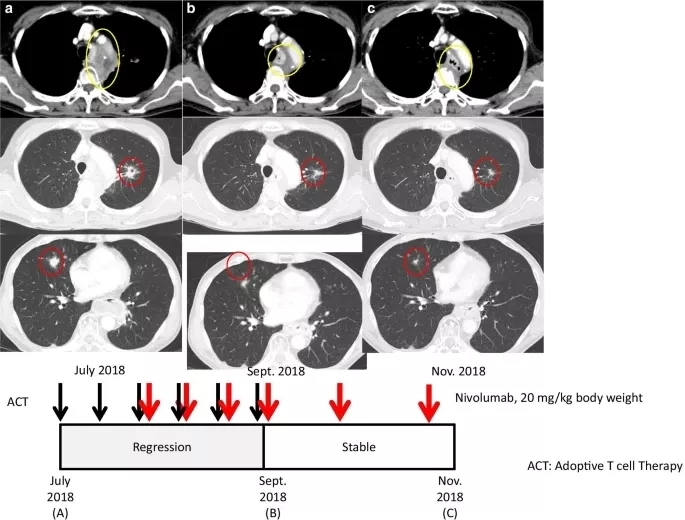

日本女性患者,于2016年2月被诊断为食管癌,时年66岁。活检和CT显示食管鳞状细胞癌临床Ⅳ期(UICC, T4N2M0)。2016年3~4月接受氟尿嘧啶/铂同步放化疗(CCRT),随后于2016年6月行食管次全切除术。手术肿瘤标本的组织病理学分析显示,食管癌处于临床Ⅱ期(UICC, T3N0M0)。2016年11月常规CT示左肺新发肺结节及纵隔淋巴结肿大,直径2.0 cm。

2016年12月因肺淋巴结转移放疗开始后就诊,并于2017年1~2月接受ACT治疗。在放疗期间,至2017年4月,患者以2~3周为间隔接受了4次αβT淋巴细胞的ACT治疗,随后患者使用氟尿嘧啶/铂/多西他赛化疗直至2018年1月。然而,2018年2月常规CT显示多发性肺转移。

2018年7月,患者报名参加了作者所在医院的一项临床试验(临床试验编号UMIN000028756)(图1a)。在开始临床试验前,作者团队利用患者的肿瘤标本评估了PD-L1表达水平,发现肿瘤组织中PD-L1表达水平小于1%。肿瘤微卫星不稳定(MSI;数据未显示)。患者以2周为间隔接受2次ACT治疗,随后以0.3 mg/kg体重的剂量接受纳武利尤单抗治疗,以2周为间隔接受4次ACT治疗,作为诱导治疗的一部分。

2018年9月19日(纳武利尤单抗启动后9周)的随访CT扫描显示部分缓解,肺转移灶和纵隔病变体积减少48%(图1b)。患者继续接受剂量为40 mg/kg体重的纳武利尤单抗作为维持治疗(时间间隔为3周)。2018年随着患者的临床进程,X线拍片显示有轻微改善(图1c),由于患者临床状态良好且存活,因此继续应用纳武利尤单抗维持治疗。患者有轻微但无症状的甲状腺功能减退,需要补充甲状腺激素,然而患者并没有显示其他临床显著的治疗相关毒性。

图1. 病例1的临床病程

轴位CT图像对应于治疗和疾病状态的时间线。黄圈表示纵隔病变,红圈表示肺转移病灶。a.(上)使用纳武利尤单抗治疗前的状态。b. 过继细胞治疗(ACT)和免疫检查点抑制剂(ICI)联合治疗后纵隔和肺转移灶的消退。在ICI维持治疗期间,反应持续(c)。黑色和红色箭头分别表示ACT和纳武利尤单抗给药(下)。